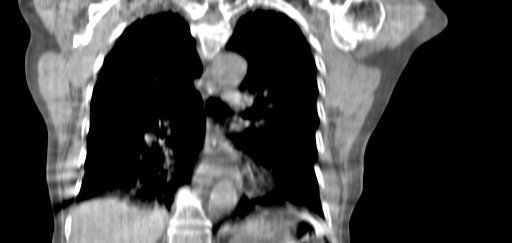

Planning CT Images

ClearRT® Images

Imaging Information

ClearRT®

Protocol

thorax-coarse-FOV50cm

Scan Length

27 cm

KVCT Imaging Time